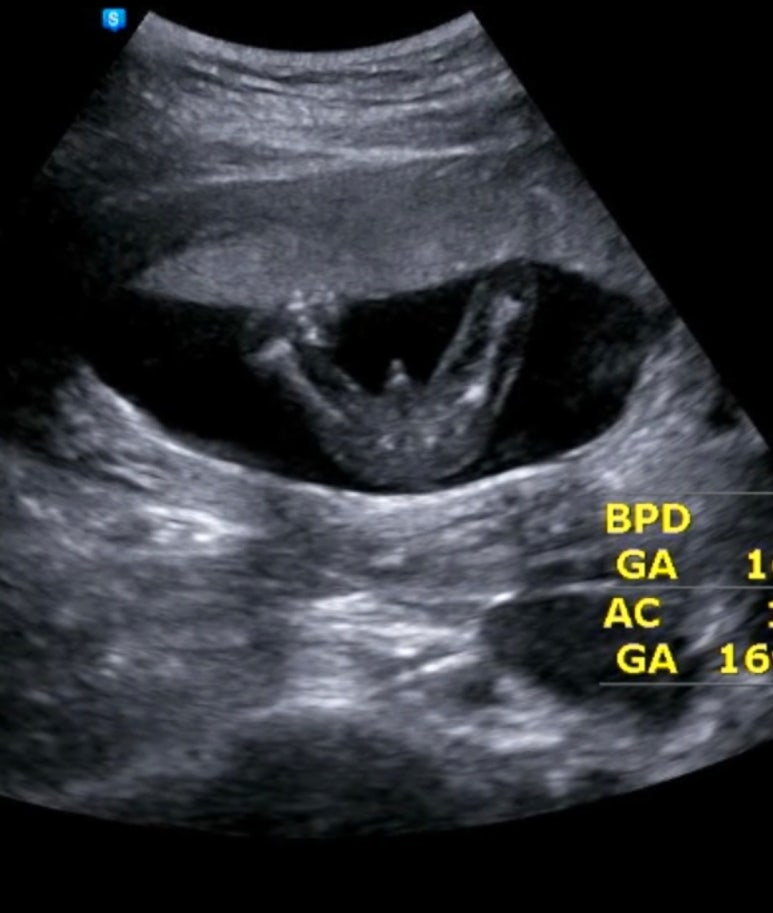

16주가 됐더니 이제 정말 성별이 육안으로 보여요! 하필 또 저렇게 쩍벌을 하고 있네요 ㅎ

우리 아들 고츄가 쏙 보이네욬ㅋㅋㅋㅋㅋㅋㅋㅋㅋㅋ

진짜 누가봐도 존재감이 남다르구나 그와중에 남편이 옆에서 크다~~ 이러고있었음ㅋㅋㅋㅋ

꼭.. 저희 아기는 옆모습을 안보여주고 앞모습을 저렇게 보여주더라구요..?

12주때도 그랬어요..ㅋㅋㅋㅋㅋ

자꾸 저 텅빈 눈과 마주침.. 입을 벌리고 있어서 웃는 얼굴처럼 보여요 ㅎ

16주 아기는 이렇게 척추도 도로로로로 이어져있고 저 중간에 검은 부분은 심장이에요!